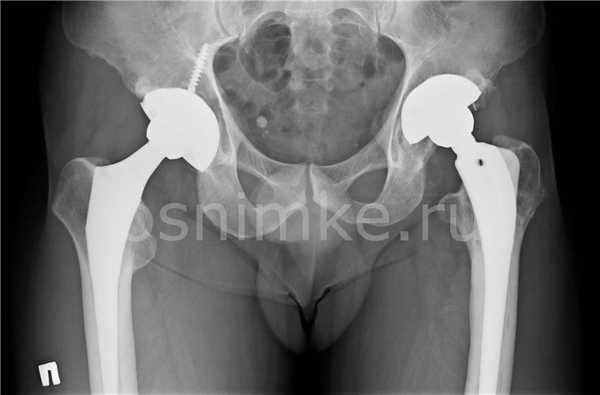

Эндопротезирование тазобедренного сустава

В послеоперационный период, в том числе после эндопротезирования суставной части таза, показан периодический контроль состояния тканей и протеза методом МРТ. Полученные данные важны для формирования прогноза и определения дальнейшей тактики ведения пациента.

Изначально боли носят нерегулярный характер, начинаются в паховой области, распространяются к колену. Со временем боли усиливаются, тазобедренный сустав теряет подвижность. Очаг некроза распространяется на всю головку бедренной кости, в месте поражения разрастается соединительная ткань, сустав теряет свою функцию, требуется эндопротезирование.

МРТ бедра показывает отек костного мозга, участки некроза под суставным хрящом с образованием серповидной полоски. На третьей-четвертой стадии отмечаются признаки импрессионного перелома, сужение суставной щели, костные разрастания, склероз и кисты в головке бедра. Изменения сустава необратимы — формируется грибовидная форма головки, деформация шейки, сглаживание суставных поверхностей.

Возможность выполнения МРТ бедра при наличии эндопротеза бедренной кости определяется составом импланта. Если в составе протеза преобладает титан, хром, процедуру можно выполнять. Эти металлы являются парамагнетиками — в магнитном поле они не нагреваются и не смещаются. Наличие примесей кобальта, никеля, железа требуют анализа состава, размера и формы протеза, поскольку эти материалы реагируют на магнитное поле, создаваемое томографом.